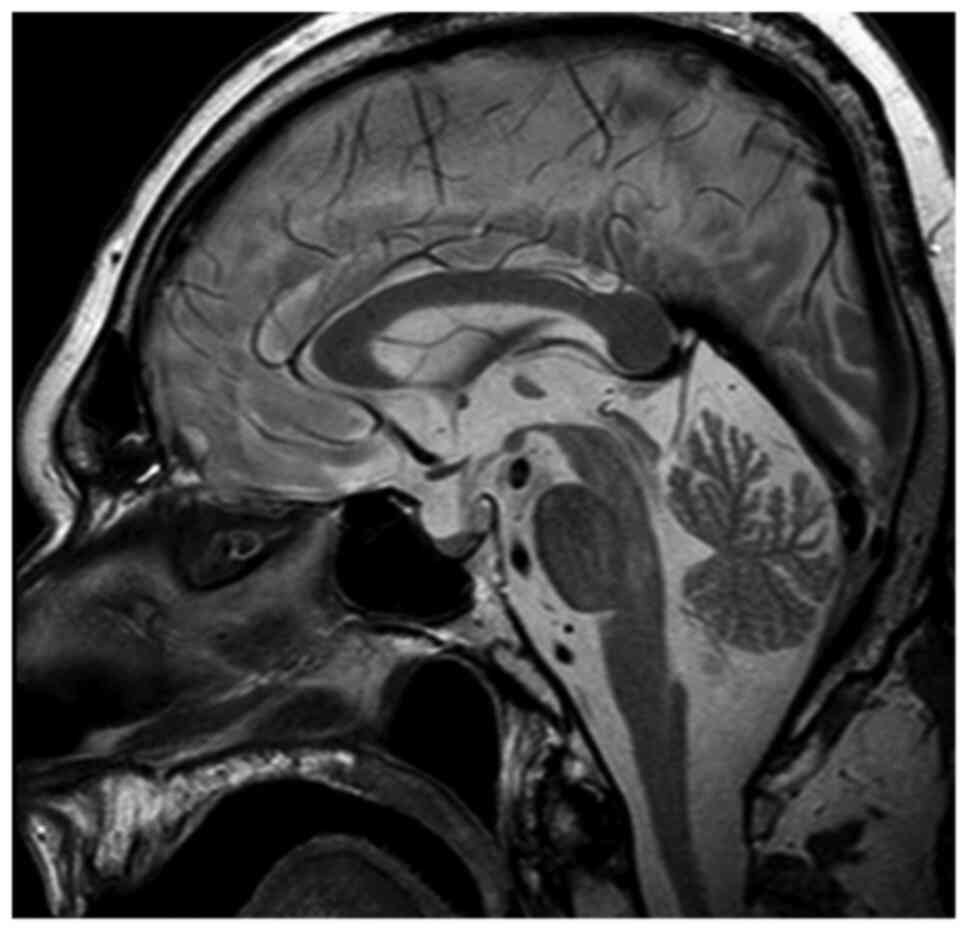

No episodes of diarrhea or vomiting were reported from recent medical history, thus potassium loss from the gastrointestinal tract was excluded. Additionally, urine electrolytes were within normal limits, hence renal potassium loss was also excluded. Therefore, endocrinological causes of hypokalemia were investigated. An adrenal protocol CT scan was performed which revealed no pathologic findings. Based on the aforementioned findings, evaluation of renin, aldosterone, ACTH and cortisol levels was requested. Τhe aforementioned tests revealed normal renin and aldosterone levels but elevated plasma cortisol levels >1,380 nmol/l (138–690 nmol/l) along with elevated plasma ACTH levels 194 pg/ml (<46 pg/ml). Measurement of 24 h urinary free cortisol revealed a value of 20,600.00 µg/gCr (1.00–119.00 µg/gCr). There was no suppression after both low-dose and high-dose dexamethasone challenge. Pituitary MRI was performed but revealed no pathologic findings (Fig. 1). Consequently, the patient was diagnosed with CS and ectopic ACTH production was considered the most likely diagnosis associated with paraneoplastic syndrome in the context of metastatic prostate adenocarcinoma.

Figure 1.

Pituitary magnetic resonance imaging T2 with no pathological findings.